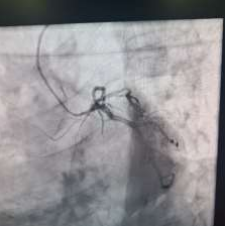

60 year old male known diabetic, hypertensive and dyslipidaemic presented with unstable angina, Coronary angiogram revealed Mid RCA pre crux lesion of 80-90% stenosis and PDA and PLV arising from Mid RCA (Fig 1). It was an angulated bend post bifurcation and hence Fielder FC wire support was taken to easily manipulate the vascular bifurcation (Fig 2) and successful PTCA+ stent to Mid RCA was done with 3x24mm Yukon choice flex stent (Fig 3& 4). TIMI III flow was achieved and post procedure period was uneventful.

FIG 3: Stent deployment